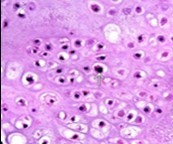

Distinction between benign cartilaginous lesions and atypical cartilaginous tumour or grade 1chondrosarcoma (ACT/CS1) can be challenging, Typically, benign cartilaginous lesions are hypo-cellular, in contrast to hyper-cellular atypical cartilaginous tumour or grade 1 chondrosarcoma 5, 6. Figure 1, Figure 2, Figure 3, Figure 4, Figure 5, Figure 6, Figure 7, Figure 8.

Figure 6.Enchondroma exemplifying lobules of hyaline cartilage composed of enlarged, vacuolated cells with uniform nuclei. Focal calcification is absent 14

Figure 7.Enchondroma enunciating lobular hyaline cartilage with constituent vacuolated chondrocytes an uniform nuclei 15.

Figure 8.Enchondroma delineating hyaline cartilaginous cells with vacuolated cytoplasm and uniform nuclei 16.